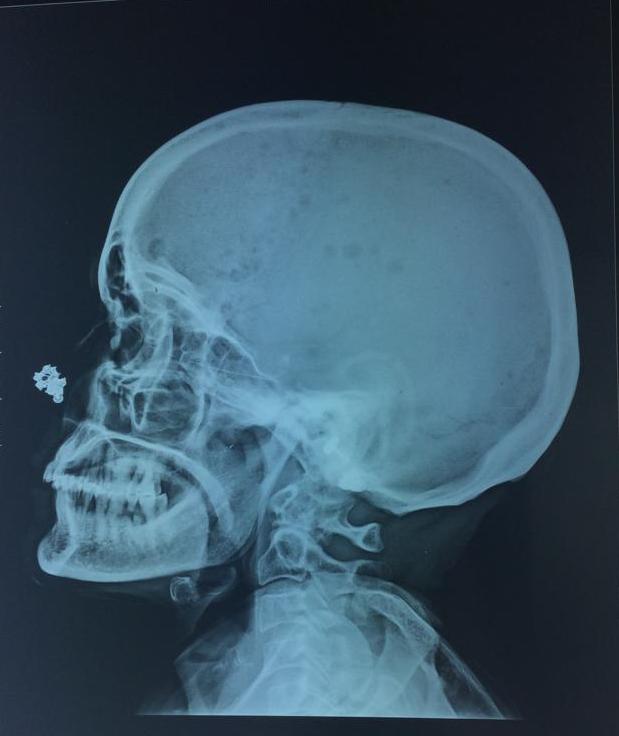

Investigations :Labs : anemia hb 4.5 with mcv 102.7 ,mch 30.8Esr 30, Platelet 45000 creatinine 2.2 with globulin 11.2 g/dl, albumin 2.6 .Corrected ca 10.In view of hypergammaglobulinemia, anemia, and renal dysfunction, there was a suspicion of multiple myeloma.X-ray skull and vertebrae were taken which showed punched out lesions in the skull and lytic lesions in vertebrae with fishbone appearance. Fig 1 and Fig2 Bone marrow aspiration showed plasma cells >50% of the marrow s/o multiple myelomaRenal dysfunction improved with adequate hydration and correction of anemia was done via blood transfusions.She is planned for chemotherapy .